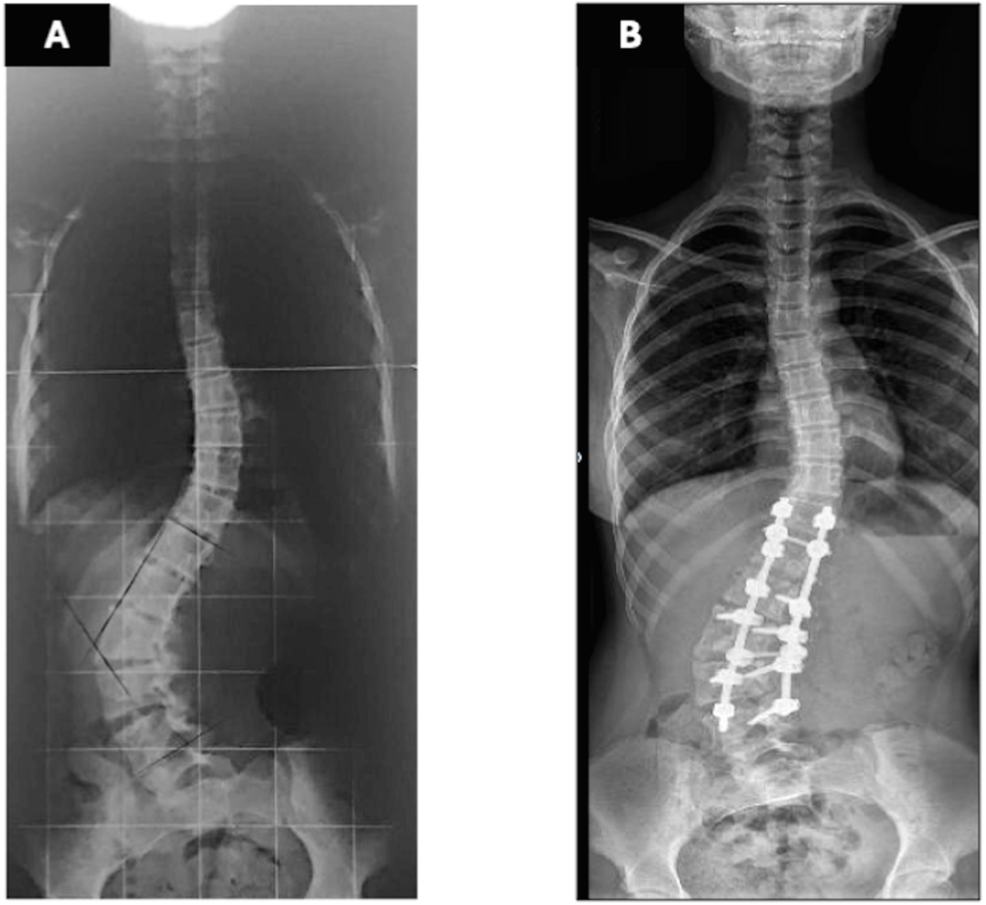

Radiographs demonstrated a 67° lumbar scoliosis due to an L3 hemivertebra fused ventrally and dorsally with L4. Previous imaging showed progression from 22° at age eight to 54° at age 11. Preoperative laboratory tests were within normal limits, including hemoglobin of 13.6 g/dL (reference range: 12.0-14.0 g/dL) and hematocrit of 40% (reference range: 36-43%). Preoperative traction radiographs demonstrated partial curve correction to 37° (Figure 1a). A computed tomography (CT) evaluation confirmed the previously described characteristics, including a 67° lumbar scoliosis caused by a ventral and dorsal fusion of L3 and L4 vertebrae. Additionally, the preoperative CT scan revealed that the IVC and aorta were located within the concavity of the spinal curve, a finding commonly observed in scoliosis cases. No other abnormalities were detected in other organs.

The patient was positioned prone on an Allen table. Bilateral pedicle screws were placed from T12 to L5, preserving the hemivertebra and L6. (L6 in orthopedic terminology denotes the lumbarization of the first sacral vertebra. This condition implies that the vertebra functions in a manner akin to a lumbar vertebra, rather than being an additional lumbar vertebra in the strict anatomical sense.) A 5.5-mm rod was inserted on the convex side, and vertebral derotation was attempted to convert the scoliotic curve into a lordotic alignment. During this maneuver, the patient developed profound hypotension (Mean Arterial Pressure < 50 mmHg) and tachycardia (heart rate > 140 bpm). Despite volume resuscitation and vasopressor administration (ephedrine and phenylephrine), hemodynamic stability was not maintained; however, approximately three minutes after reversing the derotation, blood pressure and heart rate recovered immediately. A subsequent vertebral derotation attempt made ten minutes later resulted in the recurrence of the same hemodynamic disturbance, which again resolved upon reversing the maneuver. Consequently, the surgical team opted to perform the vertebral derotation gradually, continuously monitoring hemodynamic parameters and reversing the maneuver incrementally at the first sign of instability until complete recovery was achieved. Because the correction achieved by derotation was deemed insufficient, an in-situ rod-bending technique was subsequently applied to obtain partial deformity correction (Figure 1b). Somatosensory and motor evoked potentials remained unaltered throughout the procedure. The surgery was completed without further complications, with an estimated blood loss of 500 mL and the administration of 2000 mL of Lactated Ringer’s solution.